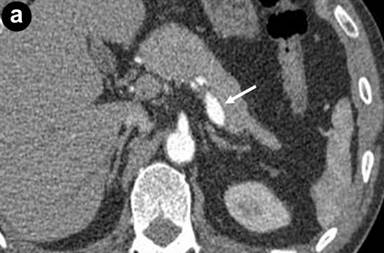

However, he was again admitted to our hospital because of epigastric pain and melena. On admission, he was hemodynamically stable. Physical examination revealed tenderness in the epigastrium. Laboratory data on admission showed mild anemia (hemoglobin 9.8 g/dL; reference range: 13.2-17.2 g/dL), an elevated white cell count (10,300 mm-3; reference range: 3,600-9,600 mm-3) and an elevated serum amylase level (1,246 U/L; reference range: 37-125 U/L). Contrast-enhanced computed tomography (CECT) demonstrated a large fusiform aneurysm (maximum diameter 10 mm) of the middle-distal splenic artery (Figure 1a), and dissection of the proximal splenic artery and celiac artery (Figure 1b). The false lumen of the dissected proximal splenic artery was partially thrombosed, and the true lumen was extremely narrow (Figure 1c). Mild enlargement of the pancreas was observed. However, no elevation of the fat density level around the pancreas was evident. There were no findings suggestive of chronic pancreatitis, such as pancreatic calcification, irregularity of the pancreatic duct and atrophy of the pancreas. CECT showed no signs of any pancreatic cyst or tumor. We made a tentative diagnosis of hemosuccus pancreaticus due to rupture of a splenic arterial aneurysm induced by acute pancreatitis.

Figure 1. a. Contrast-enhanced computed tomography (CECT) revealing a large fusiform aneurysm of the middle-distal splenic artery (arrow). b. Sagittal section of CECT showing dissection of the celiac artery (arrow). c. 3D-CT angiography showing dissection of the celiac artery (arrow head), narrowing of the proximal splenic artery (small arrow) and a fusiform aneurysm of the middle-distal splenic artery (large arrow). |